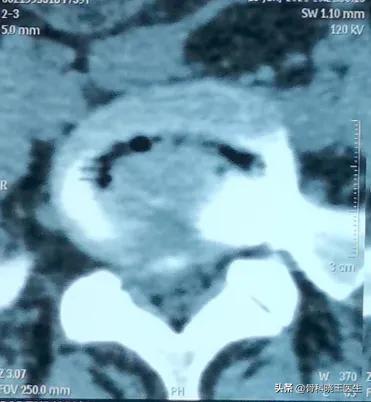

ある年に交通事故に遭い、動けなくなり、病院に行ってフィルムを撮り、CTを撮った。交通事故とは関係なく、昔からの問題である腰椎椎間板ヘルニアがあり、病院からまっすぐ家に帰るために大きな一歩を踏み出した。